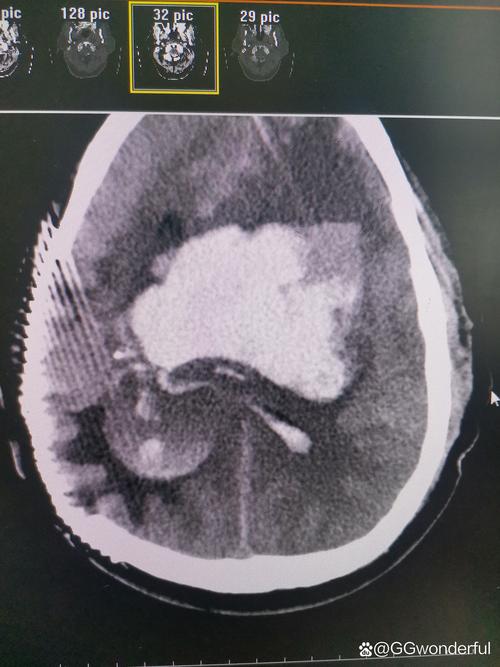

这种情况的严重性取决于几个关键因素,需要由医生通过影像学检查(主要是头颅CT)来判断:

- 出血量:出血量越大,对周围脑组织的压迫越严重,病情就越凶险。

- 出血部位:出血是否在关键功能区(如脑干、基底节区等),这直接关系到患者的生命体征和神经功能缺损程度。

- 是否形成血肿:是仅仅有点渗血(点状出血),还是形成了明显的、占位效应的血肿(团块状出血)。

- 占位效应:血肿是否会压迫周围的脑组织,导致中线移位,这是危及生命的紧急情况。